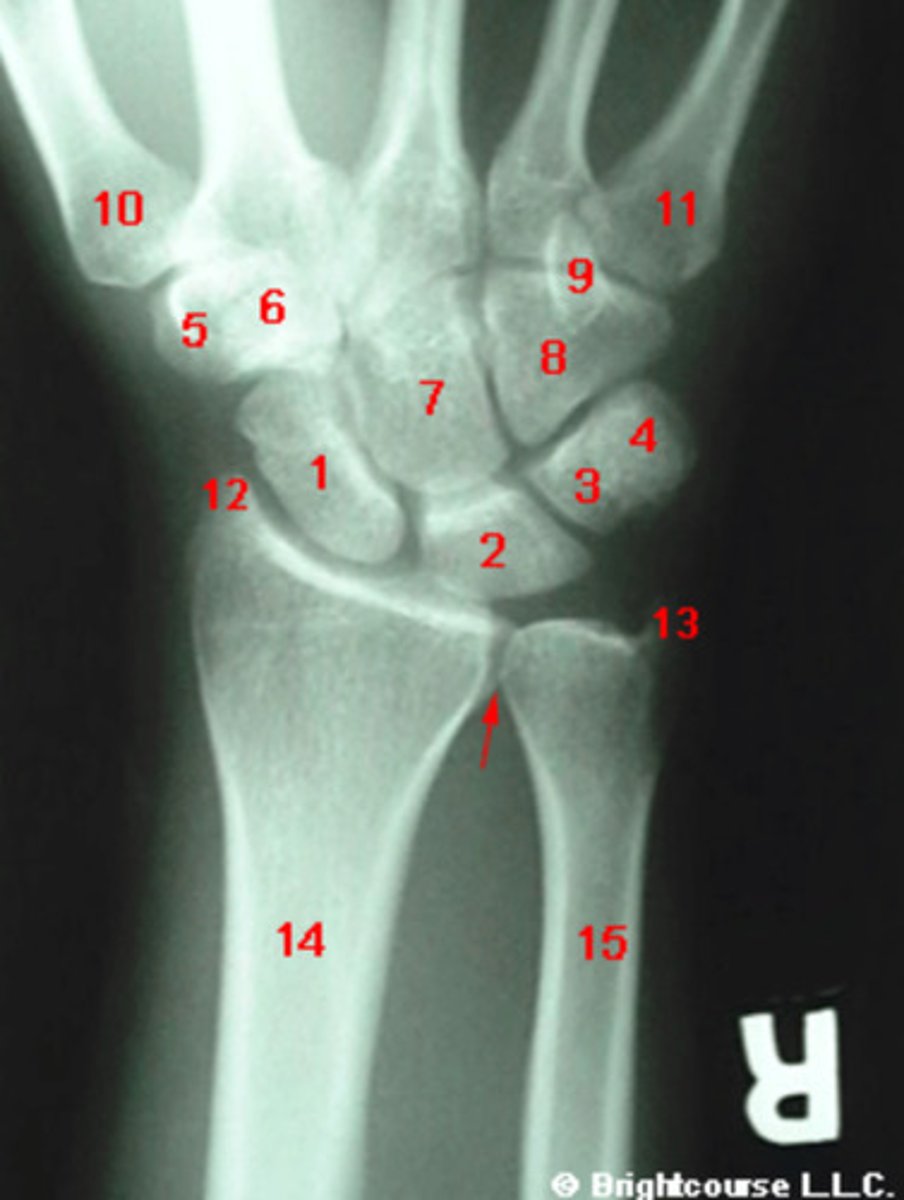

What structure is indicated by number 1?

What structure is indicated by number 2?

What structure is indicated by number 3?

What structure is indicated by number 4?

What structure is indicated by number 5?

What structure is indicated by number 6?

What structure is indicated by number 8?

What structure is indicated by number 13?

What structure is indicated by number 12?

What structure is indicated by number 7?

What structure is indicated by number 9?

What structure is indicated by number 10?